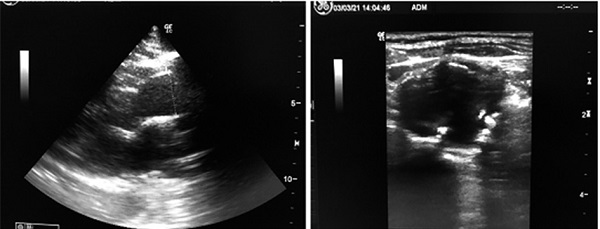

El examen físico demostró una masa pulsátil a nivel supraesternal derecho, y un soplo sistodiastólico en dicho nivel. La ecografía vascular reveló un aneurisma del TBC de 35 × 28 mm, y la presencia de placas fibrolipídicas hiperecogénicas, sin obstrucciones significativas. No se observaron dilataciones aneurismáticas en los otros vasos del cuello explorados. Se realizó un ecocardiograma que no demostró dilatación aórtica y sí una ligera elongación supravalvular de 33 mm (Figura 1). El Doppler color (Figura. 2) demostró efecto Yin Yang que rellenaba el aneurisma. Se estudiaron también las arterias de ambos miembros superiores e inferiores, no registrándose dilataciones aneurismáticas. Con este antecedente, se decidió solicitar laboratorio de rutina, hormonas tiroideas, glucemia, Hb A1C, VDRL. Como tratamiento médico se indicaron antiagregantes plaquetarios y rosuvastatina 20 mg/día. La paciente fue derivada a cirugía vascular para evaluar tratamiento quirúrgico o endovascular, intercurre con una neumopatía de la comunidad por lo cual debió ser internada, con buena respuesta al tratamiento con antibióticos. A su alta y luego de ateneo se decidió operarla del aneurisma, actualmente permanece en lista de espera para cirugía.